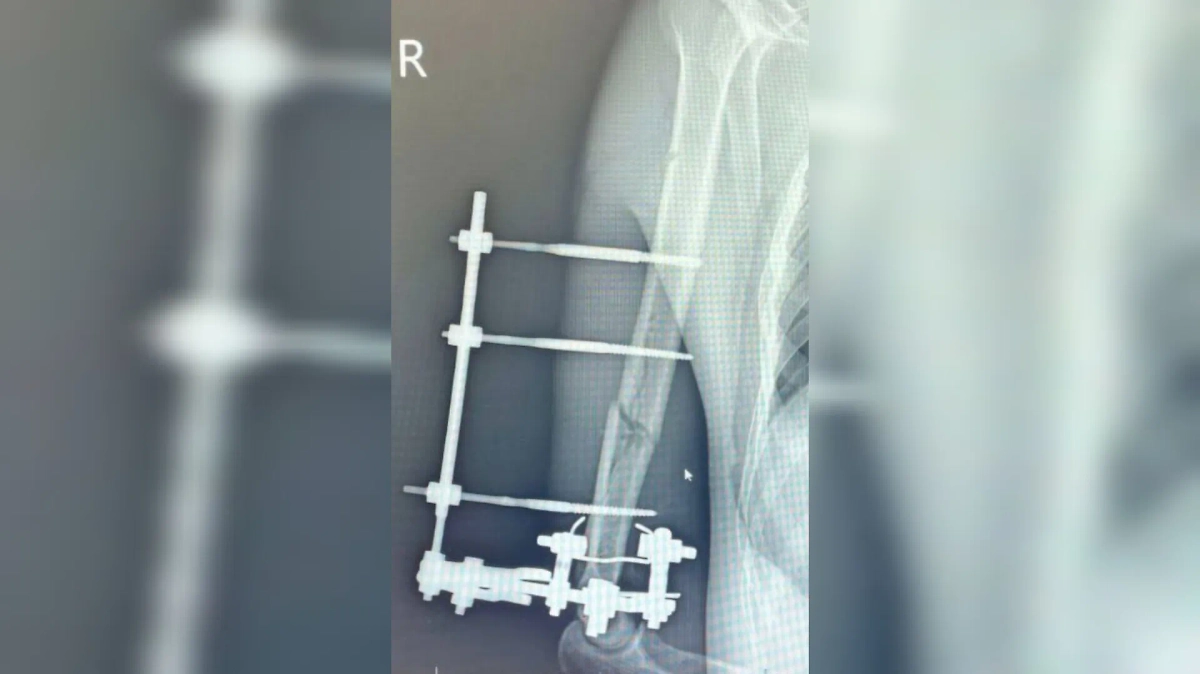

Состояние руки подмосковного мотоциклиста после проведения операции на рентгеновском снимке. Фото © Министерство здравоохранения Московской области

«Изначально были риски потери руки, но нам удалось её спасти. Мы провели хирургическую обработку, зафиксировали конечность в правильном положении. Затем выполнили остеосинтез аппаратом Илизарова», – рассказал заведующий травматологическим отделением Роберт Миллер.